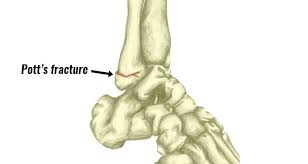

2)pott’s fracture:=

પોટ્સ ફ્રેક્ચર એ મુખ્યત્વે ટીબીયા અને ફિબ્યુલાના mediul melleiolus માં જોવા મળે છે.